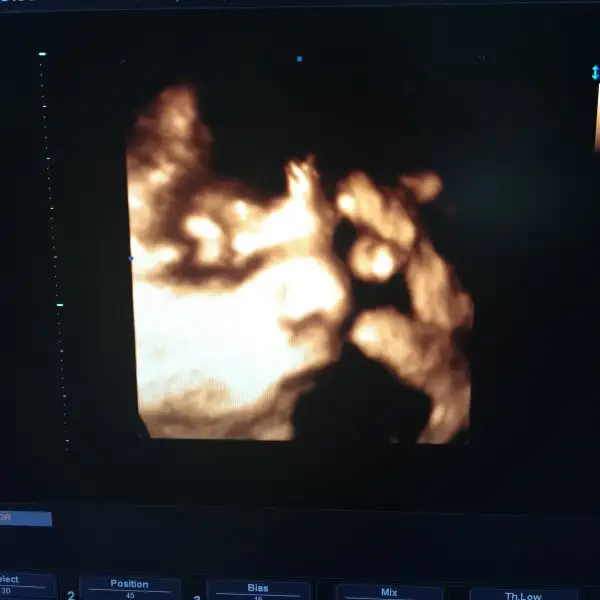

35+5 kontrolümüz vardı 2800 48 cm karın ölçüsü 1 hafta geride ama boy kilo iyi dedi doktor nstde az agrı çıktı tam kasıklarımda batma hissettiğim an sanırım ne olduğunu anladım sonunda Batmaların :) hareketi az uyuyordu sanırım evde hic durmuyordu tekrar gircm simdi çikolata yedim. Bakalım bu sefer Nasıl cıakacak:/ bu da bebişin şimdiye kadar gördüğüm en net fotoğrafı